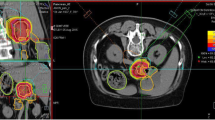

Between May 2015 and February 2019, 13 LRPC patients were irradiated with carbon ions at HIT. A median total dose of 48 Gy (RBE) was delivered in 12 fractions using an active raster-scanning technique at a rotating gantry. No concomitant chemotherapy was administered. Patient and treatment characteristics are shown in Tables 1 and 2. A representative radiation plan is shown in Fig. 2.

Radiation plan of a 59-year-old patient suffering from locally recurrent pancreatic cancer demonstrating a steep dose gradient of the performed irradiation. The patient was irradiated in supine position using two oblique posterior beams to avoid gastrointestinal toxicity. Axial (a), coronal (b), and sagittal (c) computed tomography (CT) slices and isodose lines are shown. The gross tumor volume (GTV) is delineated in green, the gastrointestinal tract is contoured in light blue. Isodoses represent a forward-calculation using an α/β ratio of 2 Gy in the local effect model (LEM) I. Therefore, the GTV seems to be overdosed. In the actually irradiated plan, an α/β ratio of 5 Gy in LEM I was used for the tumor tissue. d Dose–volume histogram of the radiation plan demonstrating adequate coverage of the GTV (green) while avoiding overdosage in the gastrointestinal tract (light blue)